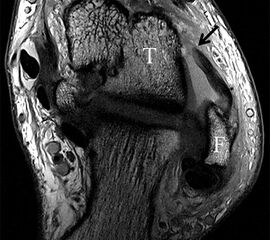

Ligamentum fibulotalare posterius (LFTP)

Das breitflächige Ligamentum fibulotalare posterius verläuft gestrafft zwischen der postero-inferioren Fibula u. dem Talus. Der typische multifaszikulär-striäre Aspekt darf nicht mit Verletzungsfolgen verwechselt werden (Abb. 13). Das Band lässt sich sowohl in der axialen als auch coronaren Ebene (Abb. 14) gut beurteilen, so dass Spezialaufnahmen normalerweise nicht erforderlich sind.